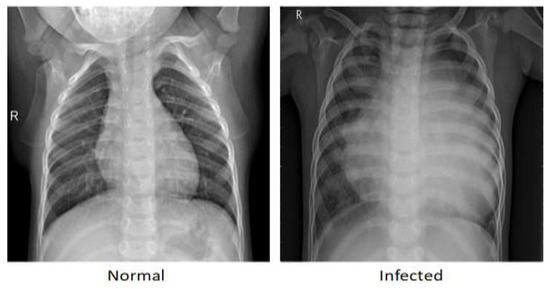

The proposed model is applied to a publicly available dataset of medical chest X-rays for pneumonia detection [34]. The digital computed radiography (CR) captured a total of 5856 images with 1583 normal cases and 4273 pneumonia cases. Figure 4 shows an example each of the CR scan for normal patients and for those diagnosed with pneumonia, in which the lungs in the normal scan are clear, while the lungs diagnosed with pneumonia look cloudy with a white area.

Figure 4. Examples of normal and of pneumonia-infected lungs.